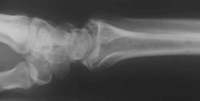

Flexionsfraktur des Radius

Die Aufsicht zeigt die Schwere der Verletzung